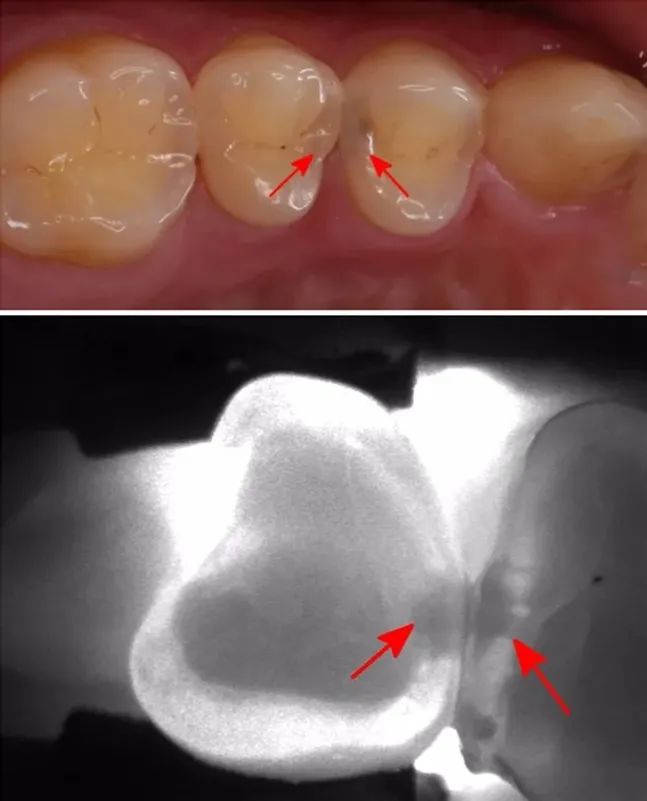

因?yàn),有些齲齒用肉眼并不能直接觀察到,它們不存在于表面,而是隱藏在深處。初期一般沒(méi)有明顯癥狀,常常難以被注意到;等到為人所察覺(jué)時(shí),往往就已經(jīng)爛得有些深了。若得不到及時(shí)治療,最終會(huì)形成牙髓炎或根尖周病,進(jìn)而影響生活質(zhì)量。對(duì)付這種隱蔽的口腔健康威脅,最有效的辦法就是定期進(jìn)行口腔檢查。

齲齒的發(fā)展是一個(gè)由淺至深的過(guò)程。起初牙齒會(huì)有點(diǎn)變色,出現(xiàn)一些小黑點(diǎn)和小黑線。此時(shí)已經(jīng)發(fā)生了淺齲,需要做藥物治療或充填治療。